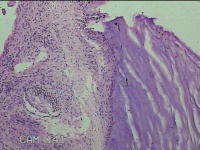

性别

女

年龄

31岁

临床诊断

宫颈上皮内瘤变

一般病史

发现宫颈CIN2 2个月。

标本名称

宫颈组织

大体所见

灰白暗红色组织2.8x1.8x0.3cm一块,表面糜烂,切面灰白暗红色,质软。

所提供图片不具有诊断价值。